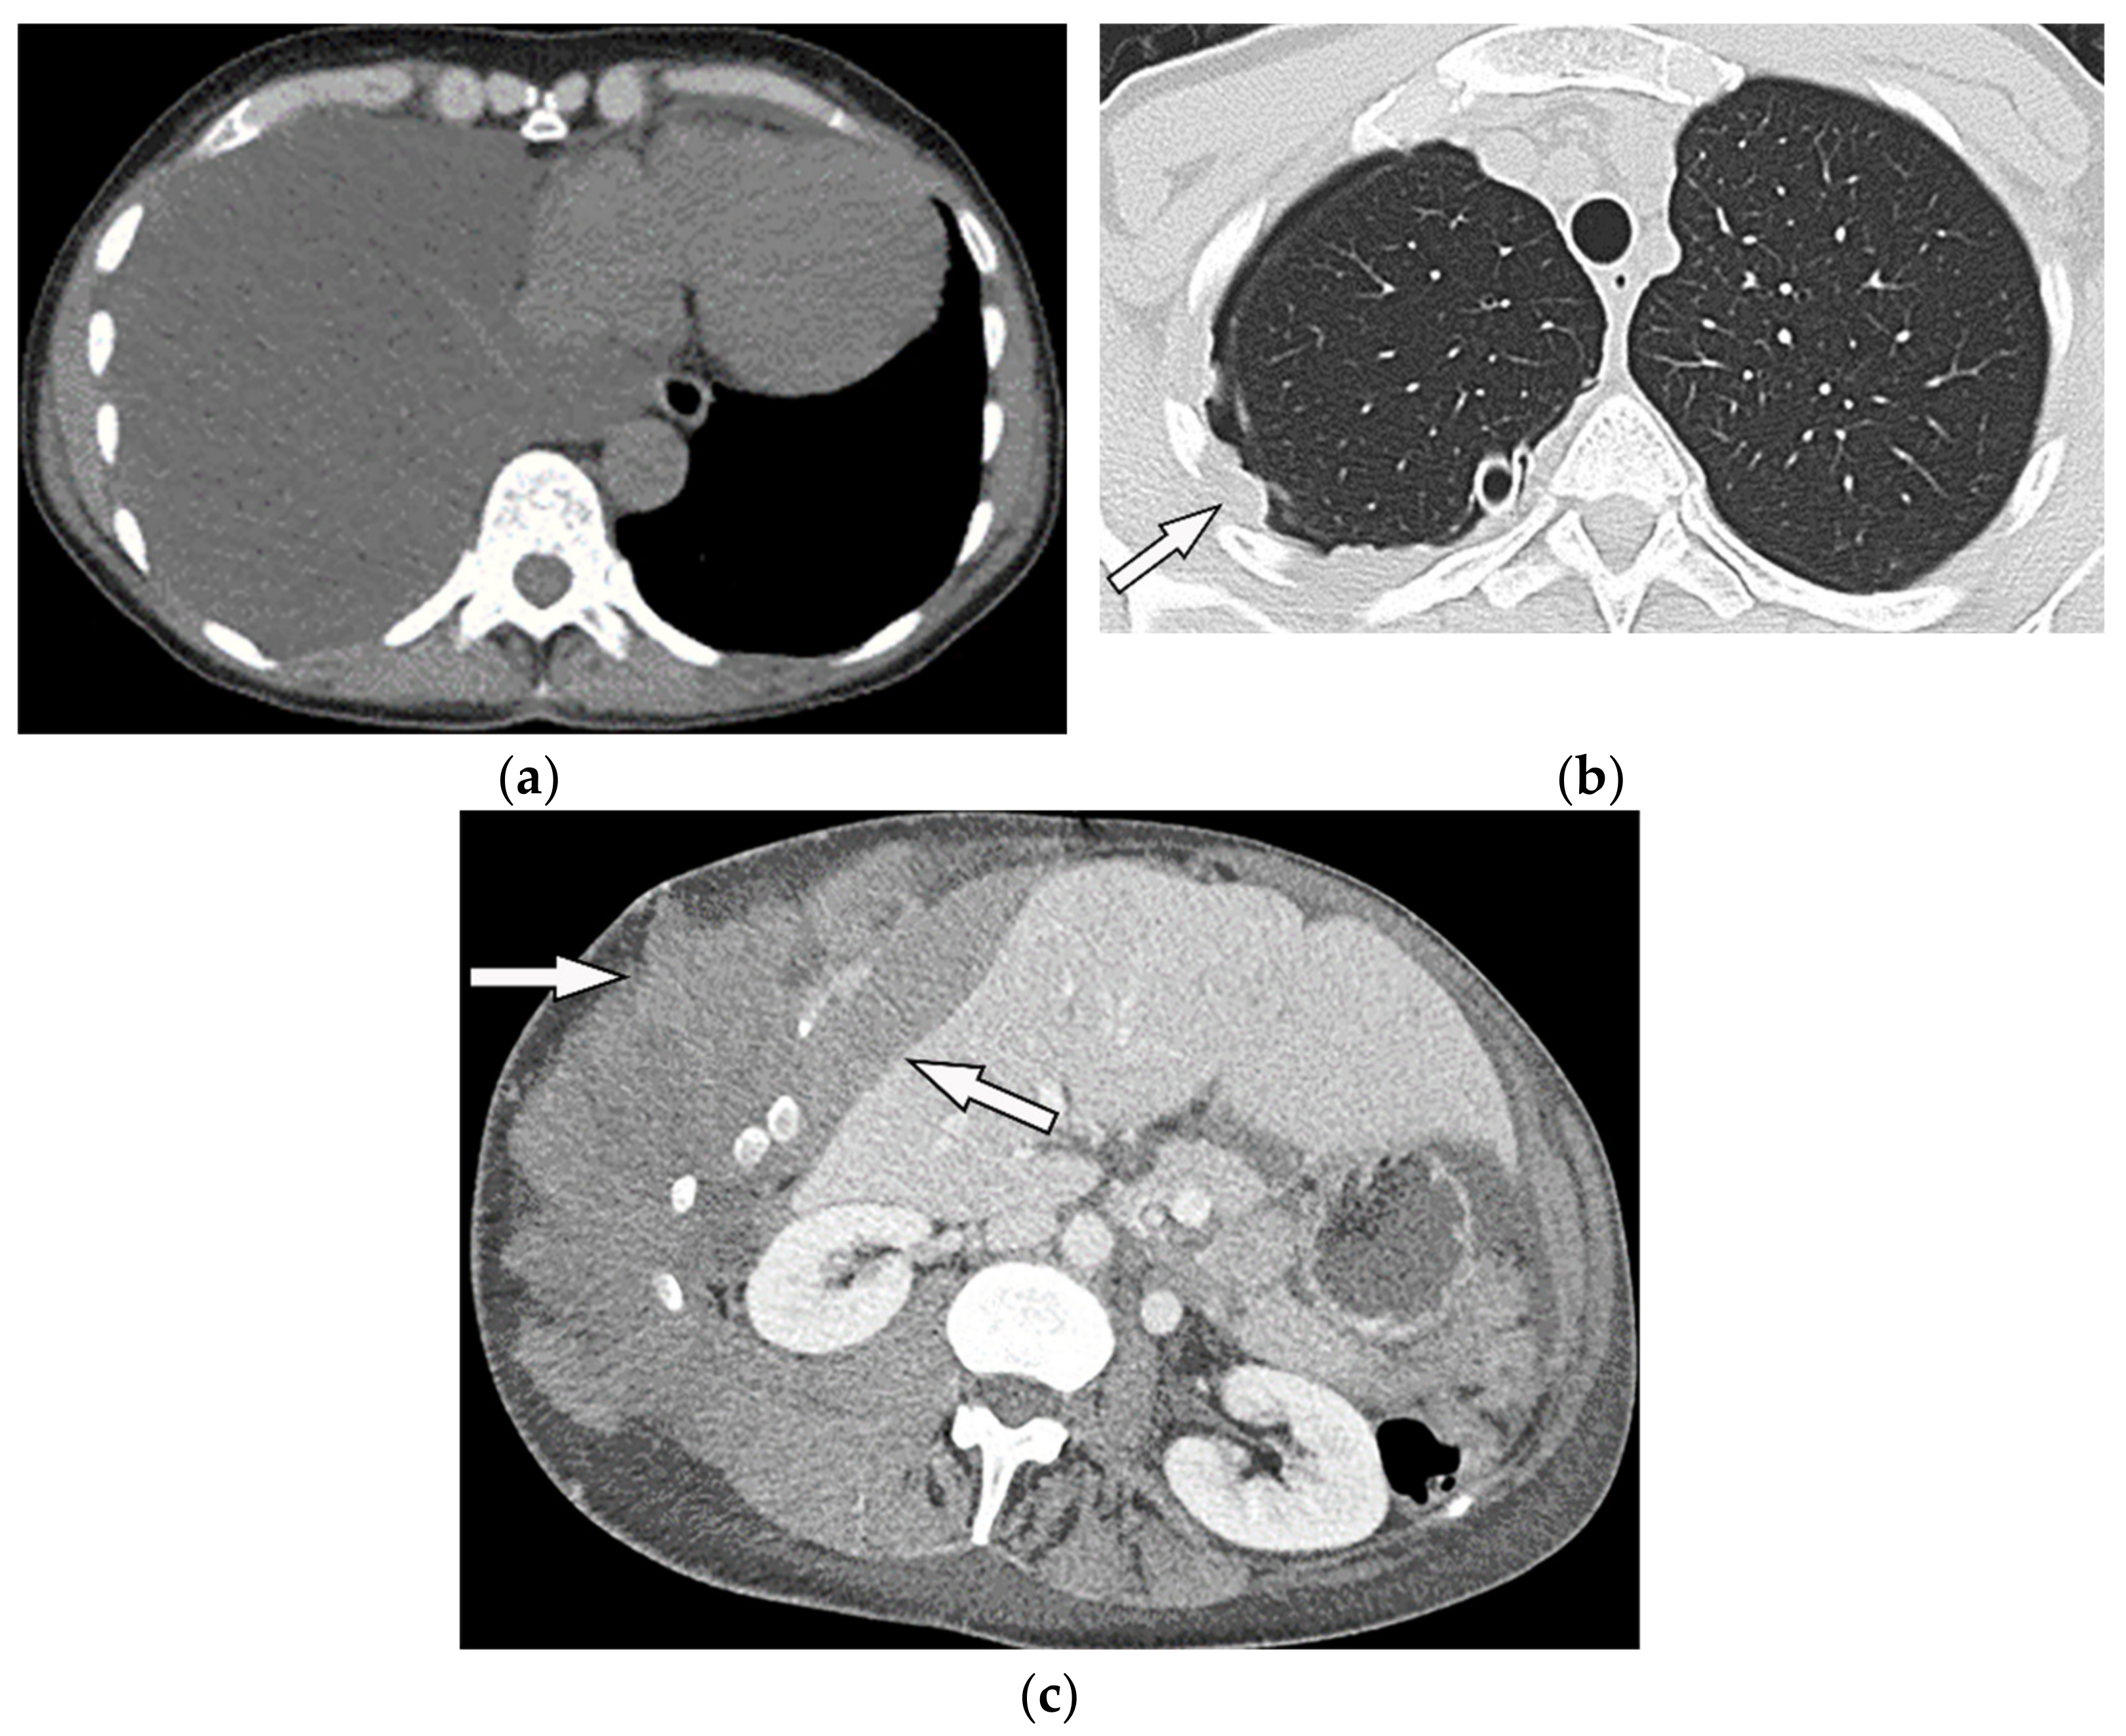

| Extramedullary hematopoiesis | Heterogeneous mass with internal foci of fat with lack of calcification. | T1W, T2W: heterogeneous with internal foci of hyperintensity in old lesions (representative of fat), the intermediate intensity with subtle or no enhancement in active lesions |

| Asbestos-related pleural plaques | Calcified or non-calcified focal pleural thickening, “Comet tail” appearance usually seen in lower lobes [48]. | T1W: hypo to isointense T2W: hypointense (due to fibrosis or calcification) [49] |